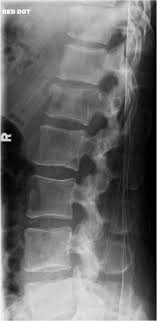

I have lumber compression fracture and i want to know how much time i need to rest in bed, currently im having totally bedrest even my wife gives me food by her hand only i standup for toilet so im in very depression and also demotiveted please help me someone does it heal by itself? This collapse can also cause pieces of bone to press on. Fluoroscopic view of a kyphoplasty procedure. In these situations, the fractures. Over the weekend i have been experiencing pins and needles in my right hand and arm, a sensation of someone pouring cold water on my left thigh and. At two months from injury, the fracture is probably still not fully stable as compression fractures take about 3 months to heal. Lumbar compression fractures can be a devastating injury, therefore, for 2 reasons. Are there effective ways to treat a compression fracture with physical therapy? The fracture looks like more of a compression fracture than a burst fracture (there is no retropulsion of the l1 body posteriorly). Anteroposterior and lateral radiographs of an l1 osteoporotic wedge compression fracture. Nonsurgical options include activity restrictions, physical therapy, and treating osteoporosis. Burst compression fracture of the l1 vertebral body is associated with a 35% loss of vertebral body height. Vertebral compression fractures (vcfs) occur when the bony block or vertebral body in the spine collapses, which can lead to severe pain, deformity and loss of height.

First, the fracture itself can cause significant pain, and media gallery. Applying heat in the first few days after an injury draws more blood to the injury site, thus. There is a 3 mm retropulsion into the spinal canal, resulting in only mild canal. Lumbar compression fractures can be a devastating injury, therefore, for 2 reasons. Compression fractures tend to heal completely in about 8 to 12 weeks. More often, the vertebra with a. Vertebral compression fractures | american association of neurological surgeons. Rarely, compression fractures occur in healthy vertebrae as a result of trauma. Anteroposterior and lateral radiographs of an l1 osteoporotic wedge compression fracture. Compression fractures of the spine usually occur at the bottom part of the thoracic spine (t11 and t12) and the first vertebra of the lumbar spine (l1). The fracture line breaches both the anterior and posterior vertebral body cortex and the anterior superior endplate. Apply the one that makes the injury feel better. A compression fracture is a type of fracture or break in your vertebrae.